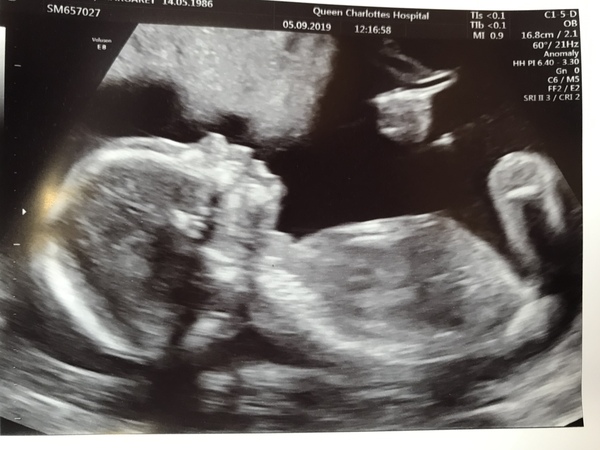

Currently 13+4 having had my dating scan today! Due date set at 8th March which is international women's day!

@strawberrye fantastic scan photos, glad all is looking good

@Strawberrye Love the scan pictures you posted on the other thread. Love how baby had its legs stretched out!

strawberrye · 05/09/2019 18:51

@KnitKitty yeah baby seemed very chilled out in there, even the sonographers commented on it!

@strawberrye saw your scan pic, it’s so clear! So pleased for you.